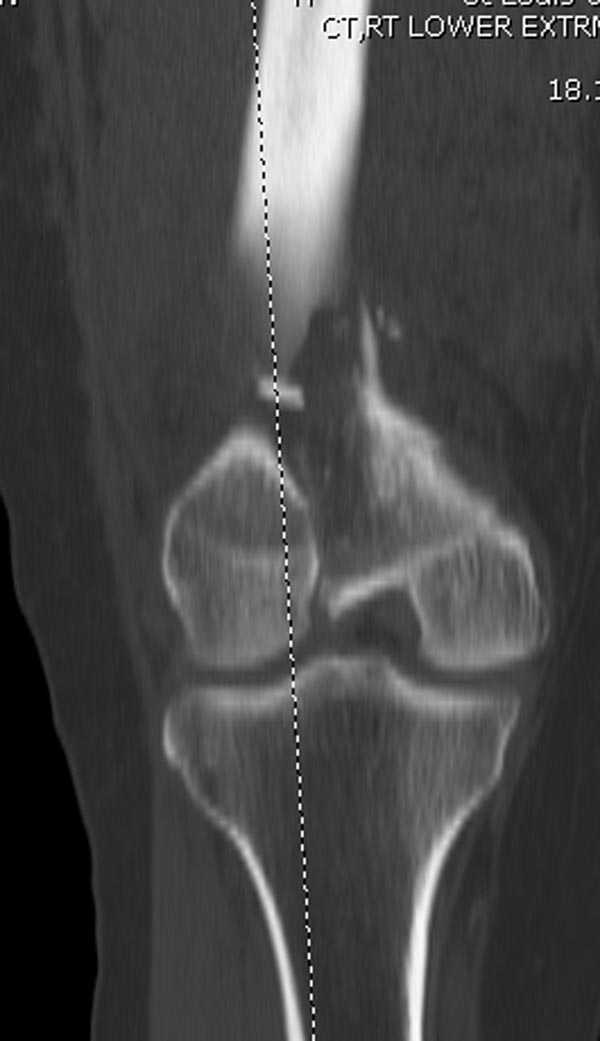

Re: Дистальный перелом бедра

Бесспорно, предлагаемый ретроградный метод имеет свои преимущества, но имеется опасность при манипуляции интрамедуллярным гвоздем расколоть мыщелки.

Раскол можно предупредить шурупами, но короткий дистальный фрагмент навряд ли позволит добиться адекватной стабильности конструкции. Стандартные гвозди не рассчитаны для таких переломов, и если все таки желаете провести фиксацию гвоздем, тогда надо заказывать специальный custom made nail т.е. с расширенной возможностью дистальной блокировки.

Поэтому такие меж и над- мыщелковые переломы более предпочтительным считается фиксировать мыщелковыми пластинами